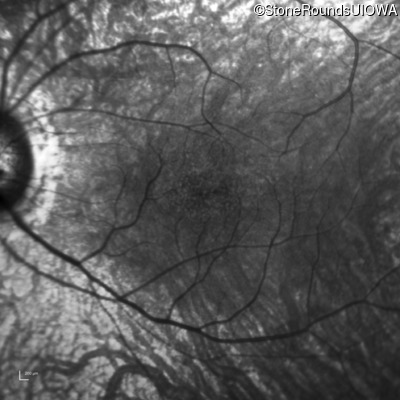

Infrared Fundus Photograph - Left - 20/50

Exemplar